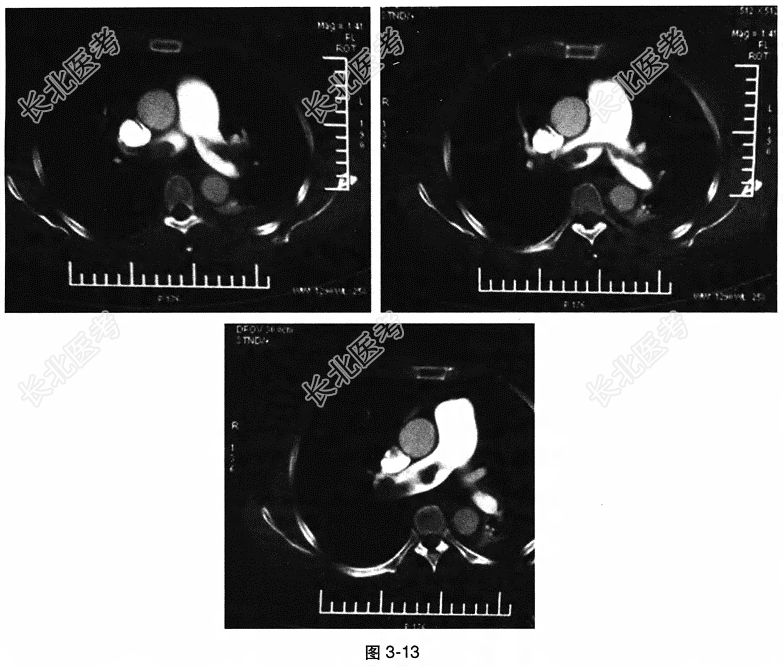

- 多项选择题4.[提示]CT肺动脉造影:双侧肺动脉主干及分支内见充盈缺损影。肺动脉主干管径超过同层面升主动脉。左侧胸腔可见液体密度影, 邻近肺组织部分膨胀不全(图3-13)。